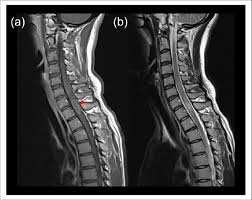

Myelitis Ursachen Symptome Und Behandlung Der Nervenkrankheit

Myelitis Ursachen Symptome Und Behandlung Der Nervenkrankheit from www.gesund-vital.de